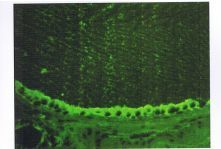

4.甲狀腺球蛋白的合成代償性增強,因此,甲狀腺濾泡常呈現以膠質瀦留為主要表現。但膠質中常含碘化不全或不夠成熟的甲狀腺球蛋白,膠質的更新也較正常為快。